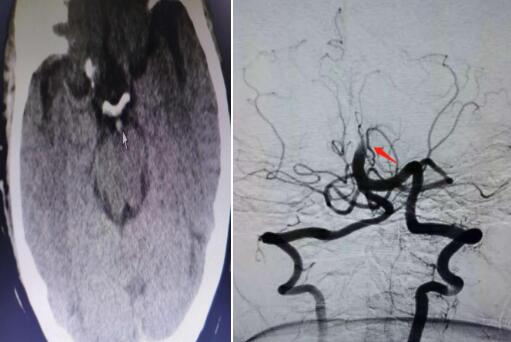

近日,我院开展市级医院首例颅内基底动脉溶栓术+取栓术,成功抢救一名基底动脉尖综合征患者。据市我院脑病科(神经内科)副主任杨波介绍,基底动脉尖综合征是一种潜在的致命性神经系统疾病。因基底动脉为脑干的主要供血系统,是呼吸、心跳等中枢的生命线,所以,一旦发生脑干缺血闭塞,如不及时抢救,患者往往“非死即瘫”...